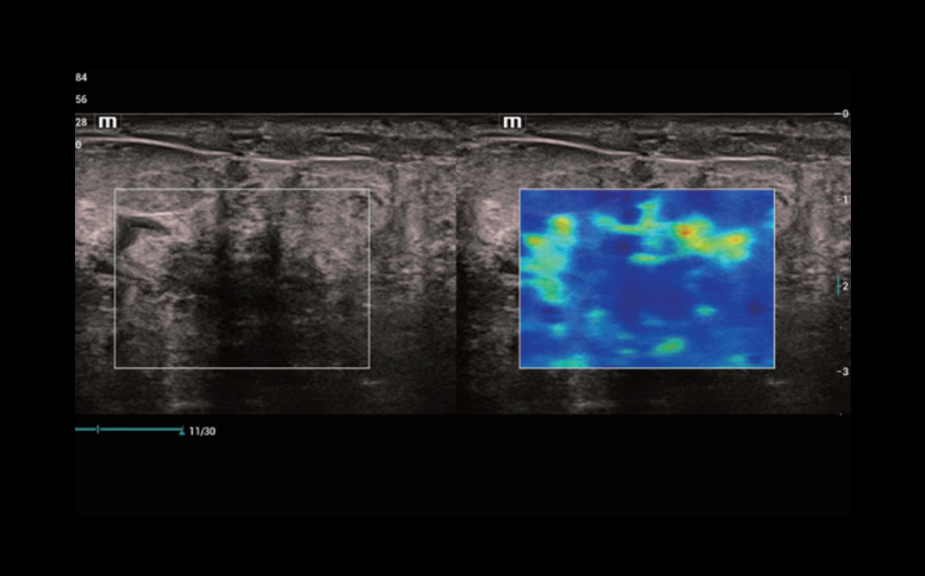

–Ě–ĺ–≤–Ķ–Ļ—ą–ł–Ļ –Ņ–ĺ–ī—Ö–ĺ–ī –ļ –ł–∑—É—á–Ķ–Ĺ–ł—é —Ā–ĺ—Ā—É–ī–ł—Ā—ā–ĺ–Ļ –≥–Ķ–ľ–ĺ–ī–ł–Ĺ–į–ľ–ł–ļ–ł: V Flow

–ė—Ā–Ņ–ĺ–Ľ—Ć–∑—É—é—ā—Ā—Ź –ľ–į—Ä–ļ–ł—Ä–ĺ–≤–į–Ĺ–Ĺ—č–Ķ —Ü–≤–Ķ—ā–ĺ–ľ –≤–Ķ–ļ—ā–ĺ—Ä–į –ī–Ľ—Ź –ł–Ĺ–ī–ł–ļ–į—Ü–ł–ł –∑–Ĺ–į—á–Ķ–Ĺ–ł—Ź —Ā–ļ–ĺ—Ä–ĺ—Ā—ā–ł –ł –Ĺ–į–Ņ—Ä–į–≤–Ľ–Ķ–Ĺ–ł—Ź –ī–≤–ł–∂–Ķ–Ĺ–ł—Ź –ļ–Ľ–Ķ—ā–ĺ–ļ –ļ—Ä–ĺ–≤–ł. –Ď–Ľ–į–≥–ĺ–ī–į—Ä—Ź —Ā–≤–Ķ—Ä—Ö–≤—č—Ā–ĺ–ļ–ĺ–Ļ —á–į—Ā—ā–ĺ—ā–Ķ –ļ–į–ī—Ä–ĺ–≤ V Flow –ĺ–Ī–Ķ—Ā–Ņ–Ķ—á–ł–≤–į–Ķ—ā —á—Ä–Ķ–∑–≤—č—á–į–Ļ–Ĺ–ĺ —á–Ķ—ā–ļ—É—é, —ā–ĺ—á–Ĺ—É—é –ł –Ĺ–Ķ–∑–į–≤–ł—Ā–ł–ľ—É—é –ĺ—ā —É–≥–Ľ–į –ļ–ĺ–ľ–Ņ–Ľ–Ķ–ļ—Ā–Ĺ—É—é –ĺ—Ü–Ķ–Ĺ–ļ—É —Ā–ĺ—Ā—É–ī–ł—Ā—ā–ĺ–Ļ –≥–Ķ–ľ–ĺ–ī–ł–Ĺ–į–ľ–ł–ļ–ł —Ā –≤–ĺ–∑–ľ–ĺ–∂–Ĺ–ĺ—Ā—ā—Ć—é –≤—Ā–Ķ—Ā—ā–ĺ—Ä–ĺ–Ĺ–Ĺ–Ķ–≥–ĺ –į–Ĺ–į–Ľ–ł–∑–į.

V Flow

–Ě–ĺ–≤–Ķ–Ļ—ą–ł–Ļ –Ņ–ĺ–ī—Ö–ĺ–ī –ļ –ł–∑—É—á–Ķ–Ĺ–ł—é —Ā–ĺ—Ā—É–ī–ł—Ā—ā–ĺ–Ļ –≥–Ķ–ľ–ĺ–ī–ł–Ĺ–į–ľ–ł–ļ–ł: V Flow

–ė—Ā–Ņ–ĺ–Ľ—Ć–∑—É—é—ā—Ā—Ź –ľ–į—Ä–ļ–ł—Ä–ĺ–≤–į–Ĺ–Ĺ—č–Ķ —Ü–≤–Ķ—ā–ĺ–ľ –≤–Ķ–ļ—ā–ĺ—Ä–į –ī–Ľ—Ź –ł–Ĺ–ī–ł–ļ–į—Ü–ł–ł –∑–Ĺ–į—á–Ķ–Ĺ–ł—Ź —Ā–ļ–ĺ—Ä–ĺ—Ā—ā–ł –ł –Ĺ–į–Ņ—Ä–į–≤–Ľ–Ķ–Ĺ–ł—Ź –ī–≤–ł–∂–Ķ–Ĺ–ł—Ź –ļ–Ľ–Ķ—ā–ĺ–ļ –ļ—Ä–ĺ–≤–ł. –Ď–Ľ–į–≥–ĺ–ī–į—Ä—Ź —Ā–≤–Ķ—Ä—Ö–≤—č—Ā–ĺ–ļ–ĺ–Ļ —á–į—Ā—ā–ĺ—ā–Ķ –ļ–į–ī—Ä–ĺ–≤ V Flow –ĺ–Ī–Ķ—Ā–Ņ–Ķ—á–ł–≤–į–Ķ—ā —á—Ä–Ķ–∑–≤—č—á–į–Ļ–Ĺ–ĺ —á–Ķ—ā–ļ—É—é, —ā–ĺ—á–Ĺ—É—é –ł –Ĺ–Ķ–∑–į–≤–ł—Ā–ł–ľ—É—é –ĺ—ā —É–≥–Ľ–į –ļ–ĺ–ľ–Ņ–Ľ–Ķ–ļ—Ā–Ĺ—É—é –ĺ—Ü–Ķ–Ĺ–ļ—É —Ā–ĺ—Ā—É–ī–ł—Ā—ā–ĺ–Ļ –≥–Ķ–ľ–ĺ–ī–ł–Ĺ–į–ľ–ł–ļ–ł —Ā –≤–ĺ–∑–ľ–ĺ–∂–Ĺ–ĺ—Ā—ā—Ć—é –≤—Ā–Ķ—Ā—ā–ĺ—Ä–ĺ–Ĺ–Ĺ–Ķ–≥–ĺ –į–Ĺ–į–Ľ–ł–∑–į.

V Flow